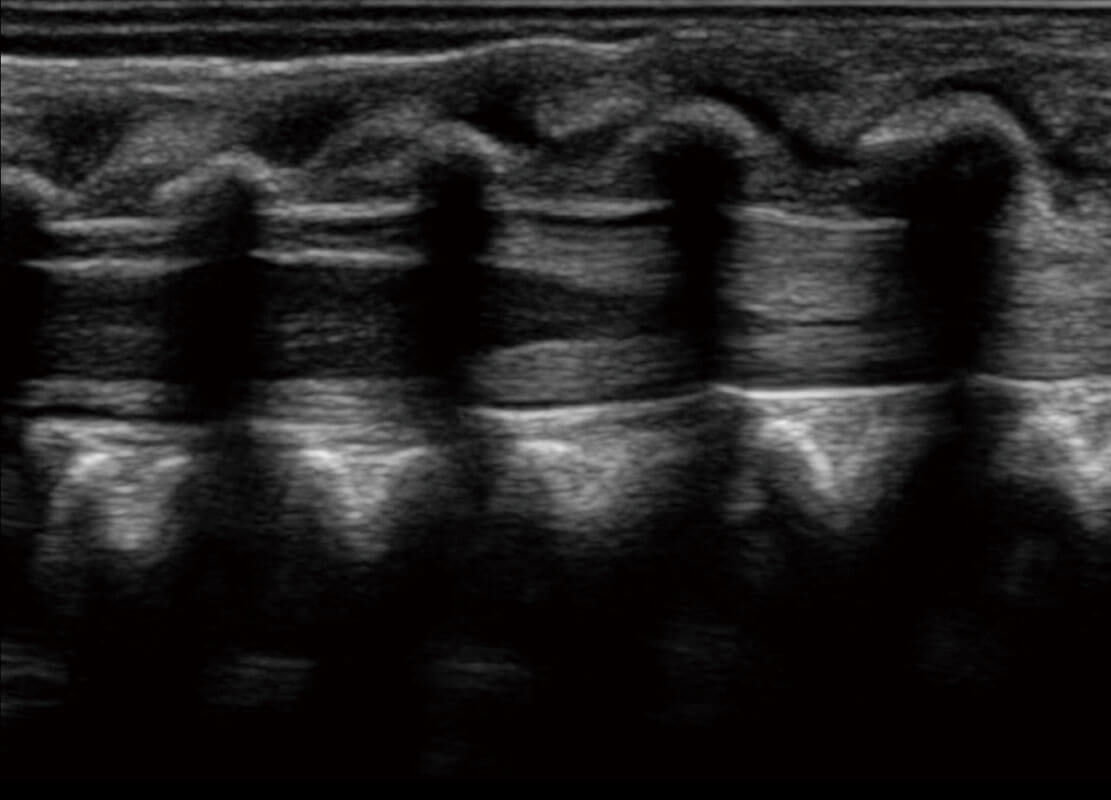

新生儿脊髓圆锥

新生儿心脏